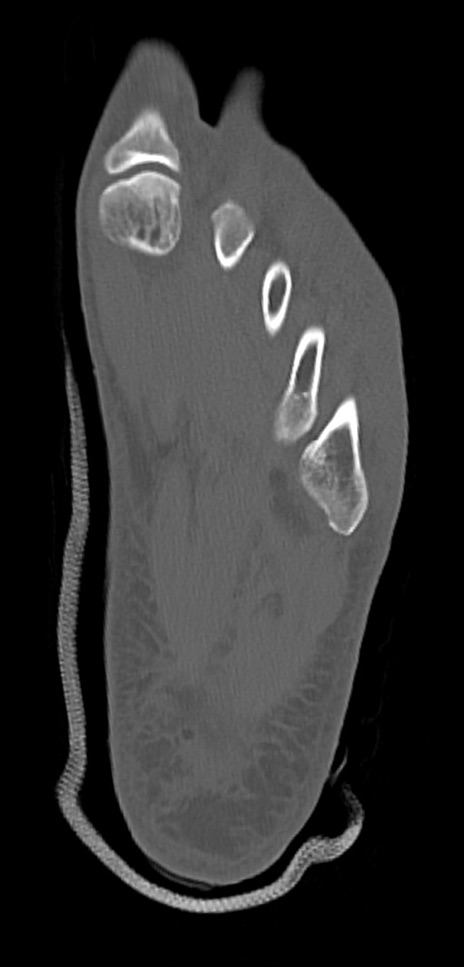

症例37 左足関節CT(横断像)

左足関節CT